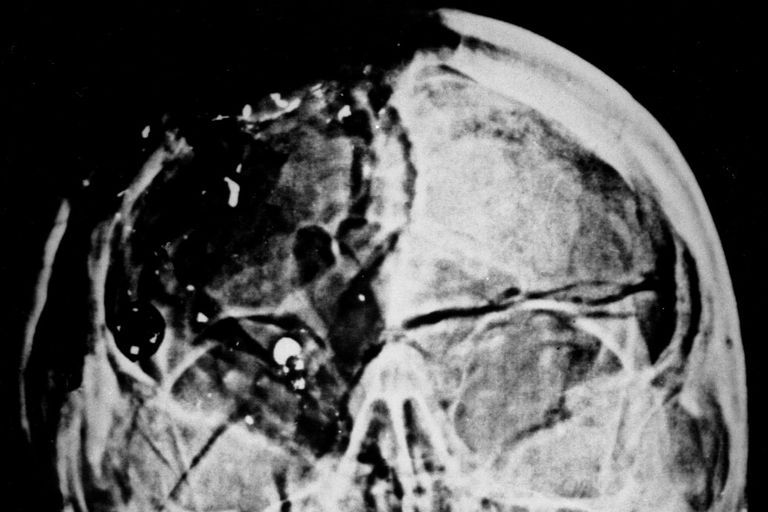

أشعة جون كينيدي - أمريكا

تم عمل أشعة سينية خلال تشريح الرئيس الأمريكي الأسبق جون كينيدي، الذي اغتيل عام 1963 في مدينة هيوستن بولاية تكساس، وحفظها داخل خزنة في الأرشيف الوطني الأمريكي، إلا أنه عندما أراد المحققون إعادة فتح القضية عام 1972 اكتشف المحققون اختفاء صورة الأشعة السينية.

ويذهب البعض للقول إن بعضا من أعضاء كينيدي نفسه سرقت من جثته، لكن لم يتم التأكد من صحة هذا الأمر.